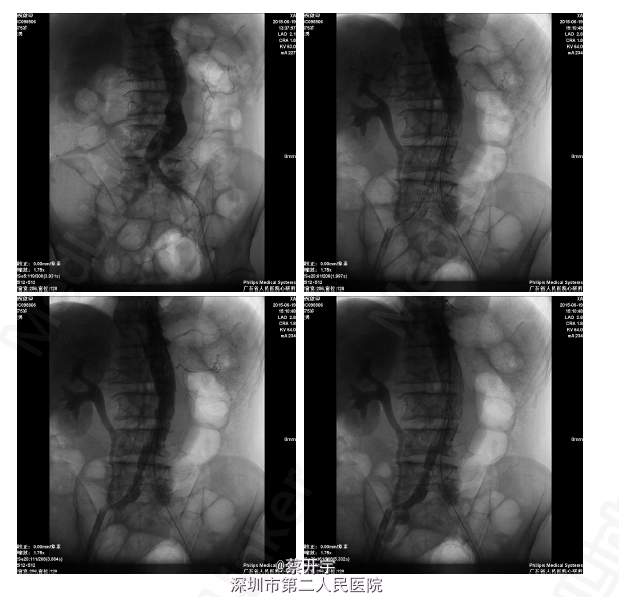

诊断:腹主动脉瘤(肾下型) 处理:排除手术禁忌症后行腹主动脉腔内隔绝术。

随访:术后患者生命体征平稳。予立普妥降脂、控制血压心率对症后出院。术后3月,电话随访患者无再发腰背痛,一般情况稳定。 讨论:男性腹主动脉瘤患者,瘤体横径大于50mm,具有手术指征,介入治疗创伤小恢复快,具有广泛前景。